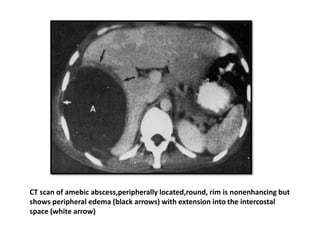

CT scan of amebic abscess,peripherally located,round, rim is nonenhancing but

shows peripheral edema (black arrows) with extension into the intercostal

space (white arrow)

CT scan ofamebic abscess,peripherally located,round, rim is nonenhancing but shows peripheral edema (black arrows) with extension into the intercostal space (white arrow)